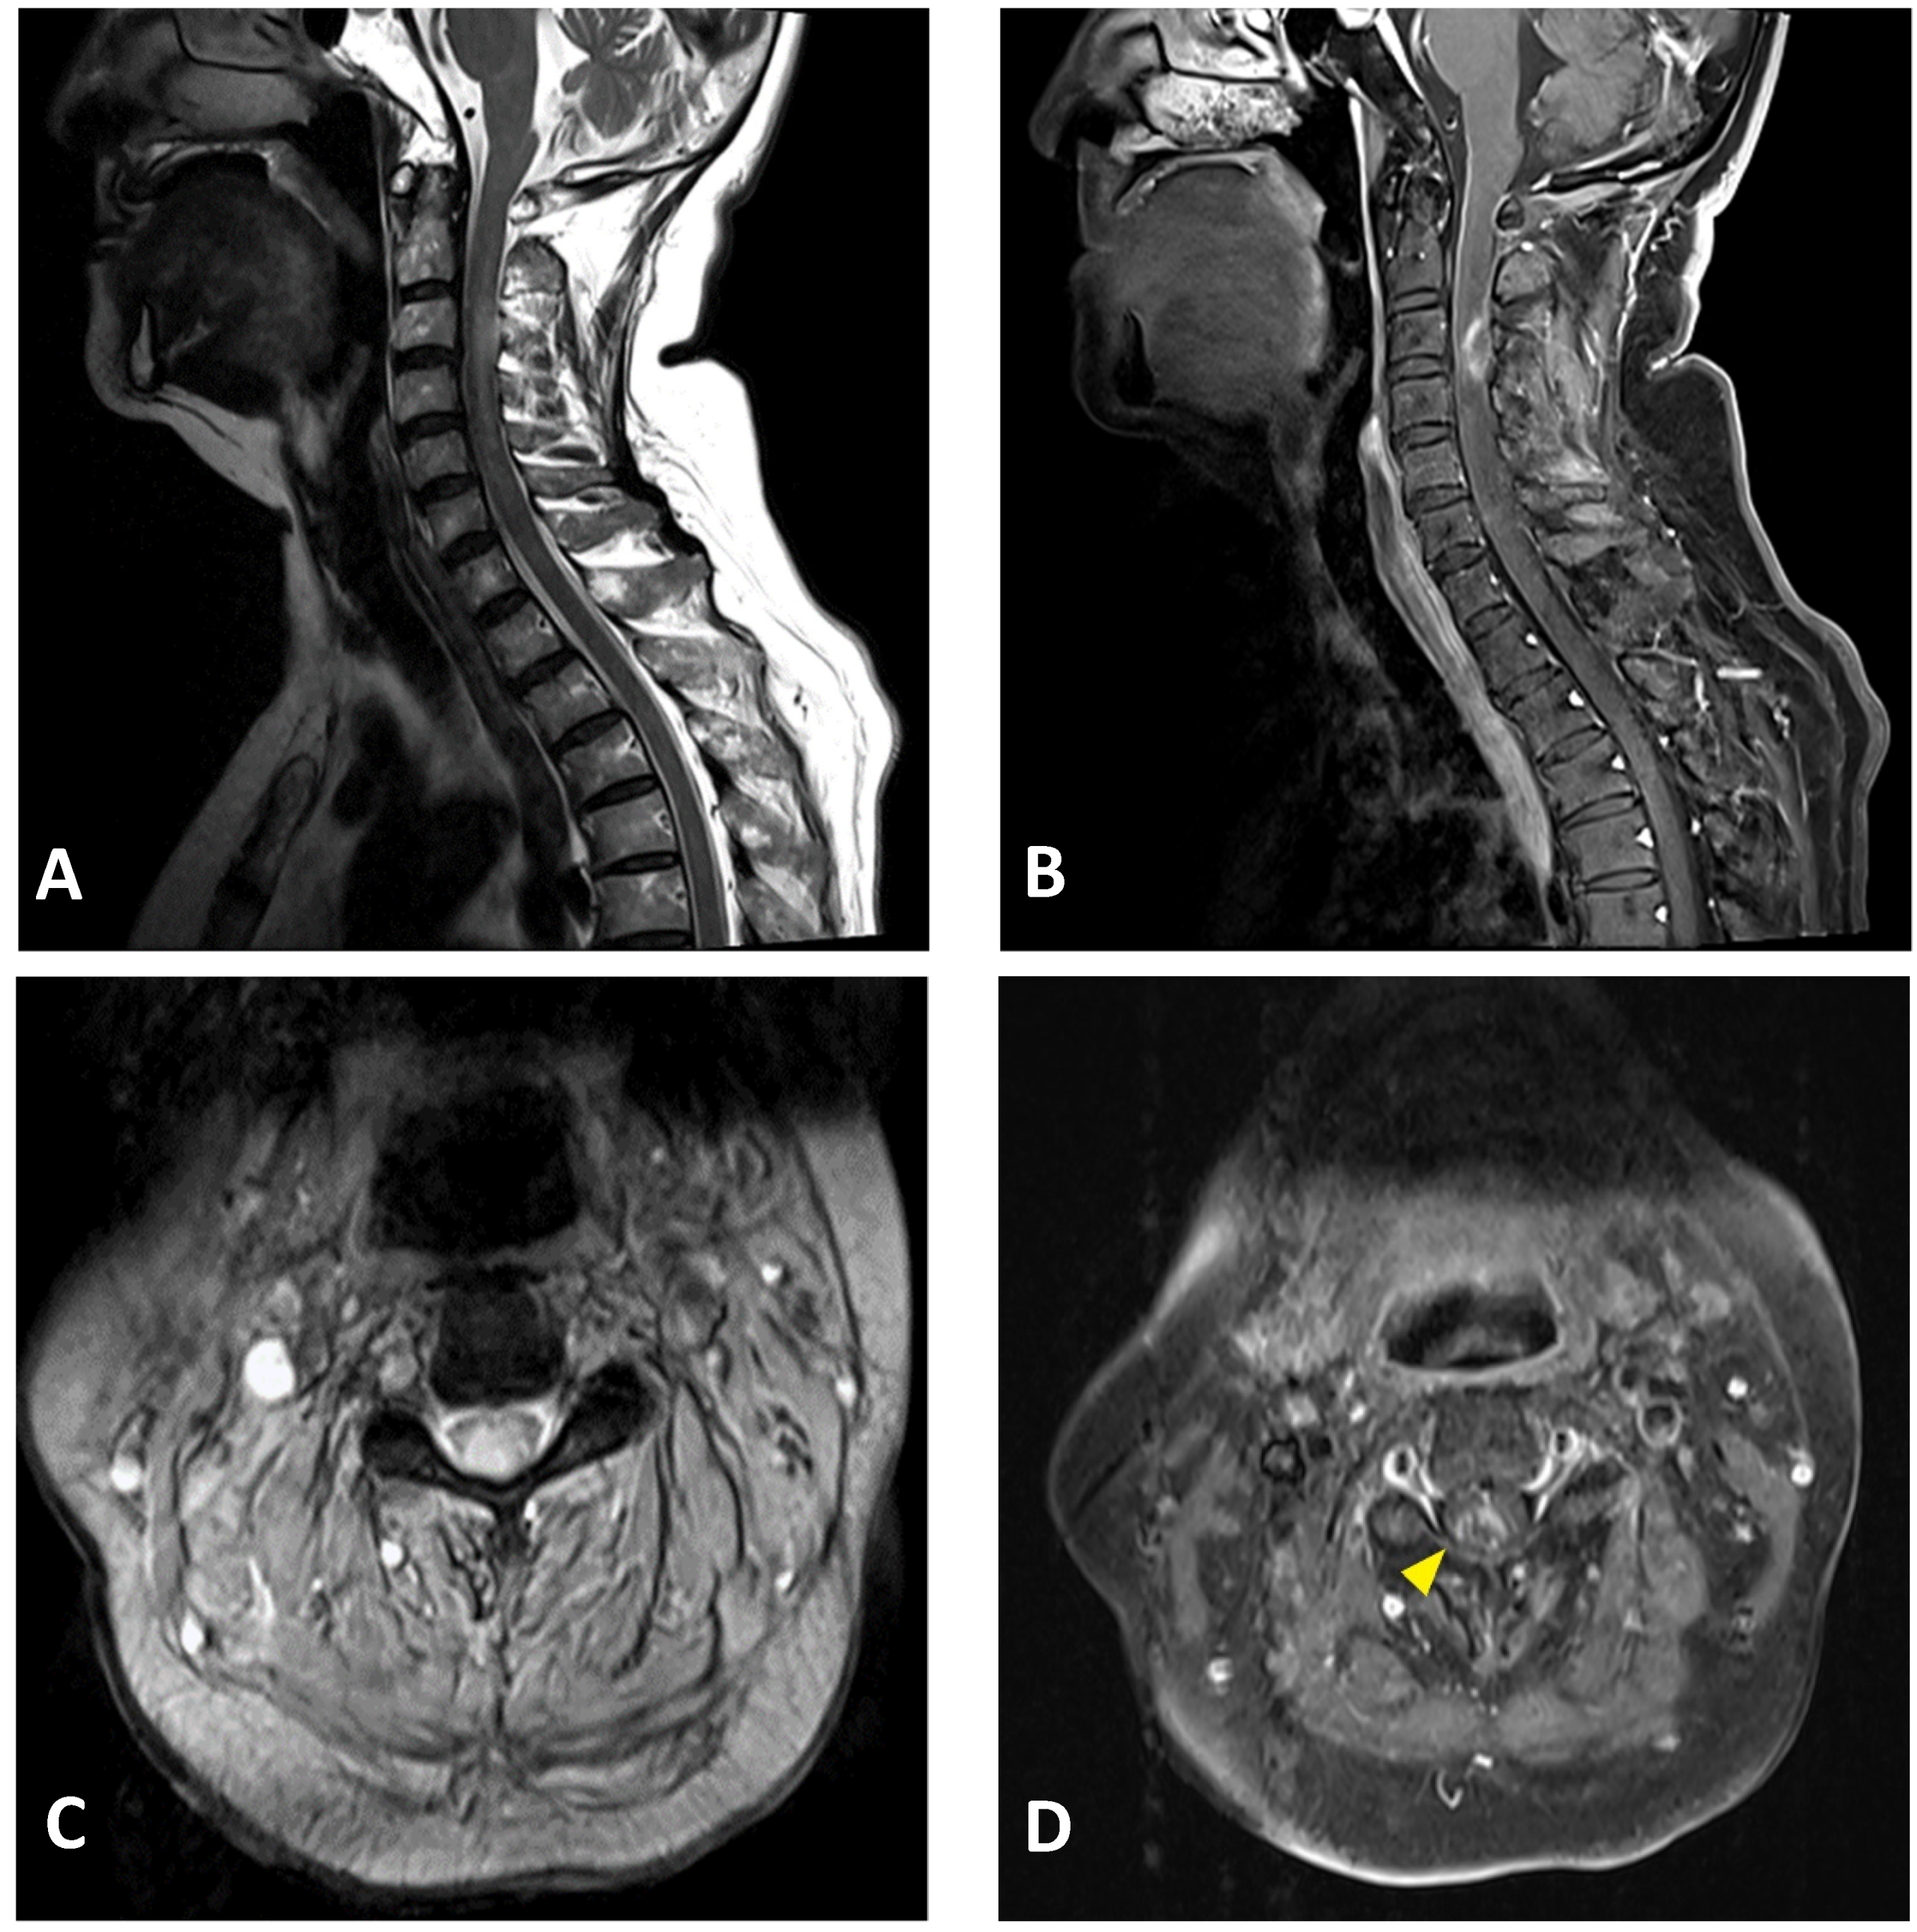

A neuroimaging study of the brain and cervical cord was performed on post-vaccination day 5, using magnetic resonance imaging (MRI). C-spine MRI revealed extensive intramedullary hyperintensity in the cervical cord at the C2–C5 levels on T2-weighted images, and at the C3 level with T1 ring enhancement of the cervical cord (Figure 2). Brain MRI and magnetic resonance angiography showed no abnormal findings. Cerebrospinal fluid (CSF) analysis showed mild pleocytosis (15/µL) with neutrophil predominance (73%) and increased protein levels (57.2 mg/dL; normal limit: 15–45 mg/dL). CSF rapid plasma reagin (RPR), treponema pallidum hemagglutination (TPPA), human immunodeficiency virus (HIV), and cytology were all negative. The multiplex polymerase chain reaction (PCR) assay FilmArray meningitis/encephalitis panel did not detect pathogens such as bacteria, viruses, and fungi in the central nervous system. Rheumatoid factor and antinuclear antibody levels were within normal limits. Serum anti-aquaporin 4 (AQP4) antibodies were negative. Somatosensory evoked potential and nerve conduction studies revealed bilateral peroneal neuropathy. The motor and visual evoked potentials were normal. Brainstem auditory evoked potentials showed right sensorineural hearing impairment. The visual evoked potential study revealed a non-significant finding. The CSF was negative for the oligoclonal band. Additionally, analyses for detecting connective tissue disorders and vasculitis profiles revealed no abnormalities (Table 1).

Figure 2.

Cervical MRI images of a 76-year-old female with longitudinally extensive transverse myelitis: (A) sagittal T2-weighted image showing hyperintensity in the cervical cord at the C2–C5 levels; (B) sagittal T1-weighted image with contrast showing ring enhancement in the cervical cord at the C3 level; (C) axial T2-weighted image showing extensive hyperintensity in the cervical cord at the C3 level; (D) axial T1-weighted image with contrast showing right-sided enhancement in the cervical cord at the C3 level (arrowhead).